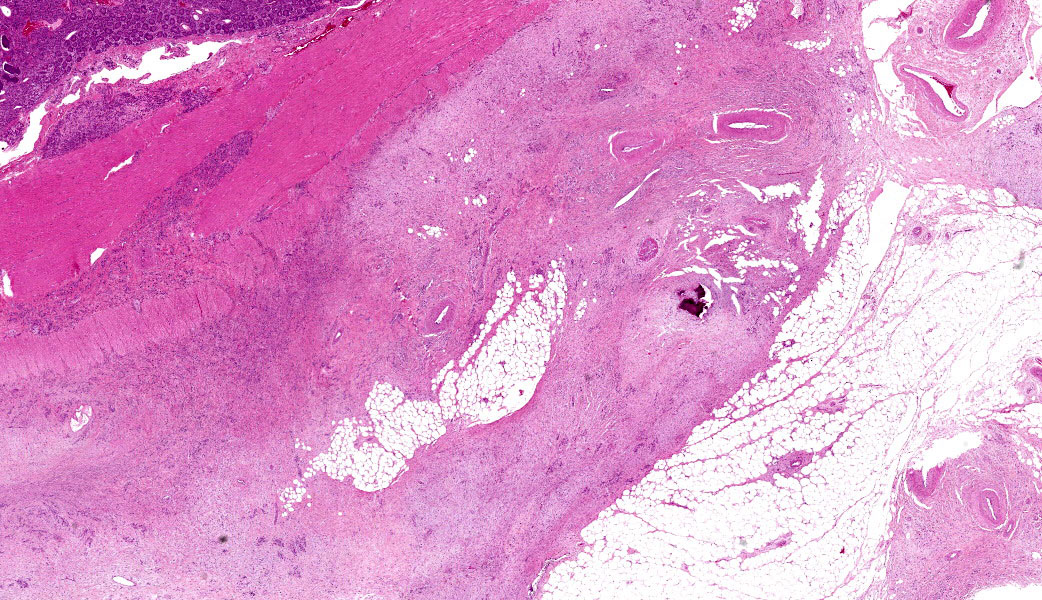

Colon: The lamina propria, submucosa, muscularis mucosa and serosa are markedly expanded by a poorly demarcated, non-encapsulated, infiltrative neoplasm composed of two populations of neoplastic epithelial cells. The neoplastic cells occur singly and in loose packets, lobules and cords, and are supported by variable fibrous stroma containing fibrocytes, fibroblasts and a light basophilic matrix. The predominant neoplastic cell is round to ovoid, 20–50 μm in diameter, with distinct cell borders, abundant finely granular basophilic cytoplasm, peripherally located oval nuclei with lightly stippled pale chromatin and single nucleoli. The secondary type of neoplastic cell is round to oval; 15-30 μm in diameter; with distinct cell borders; moderate amounts of cytoplasm containing small eosinophilic granules; single, peripherally located, large nuclei with coarse chromatin and single nucleoli. Both sub-populations of neoplastic cells exhibit moderate anisocytosis and anisokaryosis. Mitoses are rare (< 1 per HPF). There is moderate expansion of the adventitia of large vessels with neoplastic cells. The lamina propria propria is diffusely expanded by moderate numbers of lymphocytes, plasma cells, occasional macrophages and rare eosinophils. Crypts are often ectatic, lined with attenuated epithelium and containing non-degenerate neutrophils, rare macrophages and lymphocytes (crypt abscess).

- Large intestine, colon: Intestinal adenocarcinoma, sheep (Ovis aries), ruminant.

- Large intestine: Colitis, lymphoplasmacytic, chronic, diffuse, mild, with multifocal crypt abscesses.

Ileocecal junction: Intestinal adenocarcinoma.

This last case is a classic! Many thanks to the contributor for a great submission and write-up. Most participants were readily able to reach a diagnosis of intestinal adenocarcinoma in this case due to the high mitotic rate, degree of invasion the neoplasm into abluminal tissue layers, and the striking desmoplastic response. The deep infiltration from the mucosa outwards allows for a strong argument of a primary intestinal adenocarcinoma rather than a metastatic carcinoma. Intestinal adenocarcinomas tend to invade from the mucosa deep into and run laterally through the submucosa and subsequent layers.

Despite being able to reach a diagnosis, most participants struggled with the specific anatomic location for this tissue. After much back and forth, the consensus amongst conference-goers was that this is likely representative of the ileocecal junction or close to it, since there are features of both small and large intestine on opposite ends of the H&E slide. While there are crypts, mucus glands, and subcutaneous fat consistent with large intestine visible on one side, there are also villi on the other, most clearly seen associated with and around the neoplasm.

Lastly, there are notable mucosal erosions with regional neoplasia-associated architecture disruption that most participants felt was likely the cause of the inflammation present in the slide rather than an additional primary enteritis. As such, this is reflected in the JPC morphologic diagnosis, which focuses solely on the neoplasm and considers the other changes to be secondary.